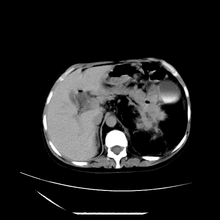

女性,41岁,发现左腹部包块3年,现行ct检查,检查前做过静脉肾盂造影。

脾脏增大,左肾后方脂肪增多,脊柱前方脂肪增多,左肾窦脂肪增多,左肾变形,双肾积水以左侧为著,左肾内侧及上方见环形软组织肿物影,内部低密度区,考虑1盆腹腔/腹膜后及左肾窦脂肪增多症2左肾内侧病灶可能为左肾上腺病灶,可能为脂肪增多的原凶

1)考虑左肾替代性脂肪瘤病;不排除左肾错构瘤。2)双肾积水。

肾窦脂肪瘤病及肾替代性脂肪瘤病被认为是脂肪增殖程度不同的一种疾病。正常情况下肾窦内有少量脂肪组织充填,在某种情况下肾实质会发生萎缩,而以肾窦、肾门为中心脂肪或(和)纤维组织可出现增殖,当增殖局限在肾窦、肾门区时称为肾窦脂肪瘤,若同时部分或全部取代了萎缩破坏的肾实质时称为肾替代性脂肪瘤病。

ct典型表现为以肾窦肾门为中心大量弥漫性脂肪积聚,鹿角状结石及萎缩的肾实质。合并肾周感染时,肾轮廓不清,周围有粘连性改变。

诊断主要需与含脂肪的肾肿瘤加以区别,如血管平滑肌脂肪瘤、脂肪肉瘤、脂肪瘤

诊断rsl的必备条件是肾窦、肾门的脂肪组织增生和肾实质的萎缩,而且本例因为ivp后扫描不好判断有无肾结石但可能性较小;另外,占位效应显著,脾后缘都受压了,肾门以下肾实质残缺,支持肾脏错构瘤.